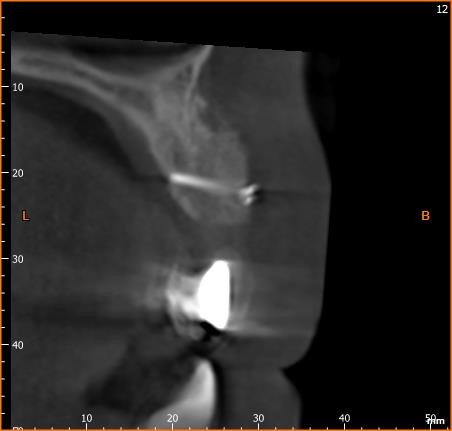

4/28 - CBCT scan: Very large horizontal offset and massively reduced bone volumeBlock augmentation with maxgraft® in the maxilla - Dr. R. Cutts